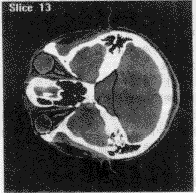

医生依自身经验勾画出手术中要避开的重要功能区、指定手术路径。图4为其中一个层面上勾画出的眼球、脑干和视神经。图5为图4中区域边界的采样点。手术中心和手术起点的指定在其他层面上,此处不再显示。

图 4 其中一层面上勾画的区域

图 5 对图4区域边界的采样

判断手术路径与勾画的重要功能区的位置关系,根据所赋代价值,计算出手术路径的风险,并显示穿越的区域,图6为其中一条手术路径的判断结果,提示医生该路径穿越了重要功能区,该方案不合适,需要重新指定手术路径。

图 6 一条手术路径的判断结果